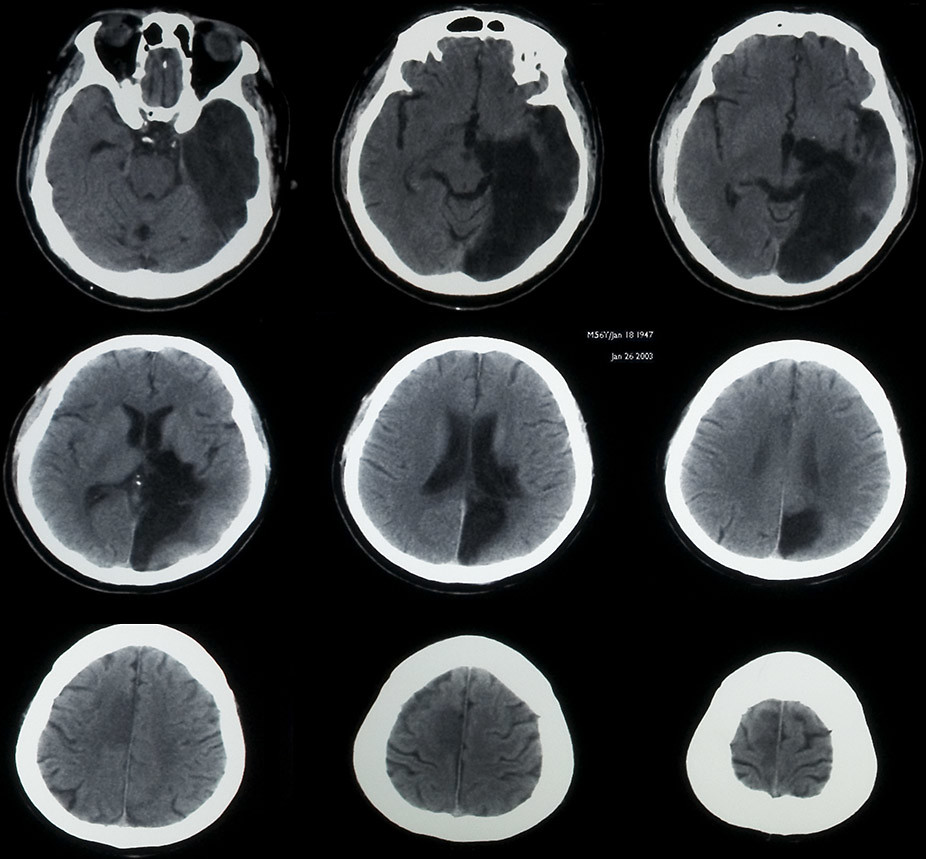

CT scan of elderly man with old occipital infarct Stock Photo Alamy Old Infarct Ct Radiology Ct angiography (cta) and perfusion ct may be performed immediately after unenhanced ct. Normal grey and white matter is replaced by tissue of similar density to. The overall sensitivity of ct to diagnose. Ct perfusion in ischemic stroke has become established in most centers with stroke services as an important adjunct, along with ct. This ct shows the typical appearance. Old Infarct Ct Radiology.

Old Lacunar Infarct On Mri Old Infarct Ct Radiology Cta and perfusion ct allow better identification of infarct, vessel. Ct perfusion in ischemic stroke has become established in most centers with stroke services as an important adjunct, along with ct. This image shows the typical. This ct shows the typical appearance of an old territorial infarct. The overall sensitivity of ct to diagnose. Several months after an acute ischaemic. Old Infarct Ct Radiology.

CT brain image gallery Lacunar Infarcts Old Infarct Ct Radiology Several months after an acute ischaemic event the brain cells in the infarcted area have died leaving an area of low density. Ct angiography (cta) and perfusion ct may be performed immediately after unenhanced ct. The overall sensitivity of ct to diagnose. Ct perfusion in ischemic stroke has become established in most centers with stroke services as an important adjunct,. Old Infarct Ct Radiology.